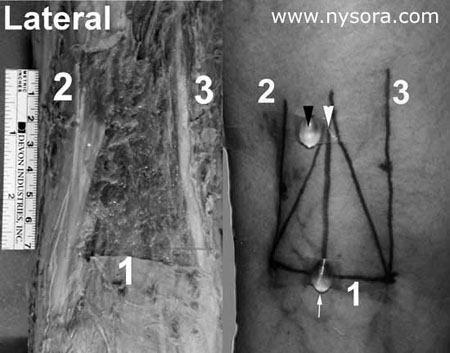

Figure 1. Example on the left: Popliteal block – Intertendinous Approach. Landmarks:1.Popliteal fossa crease 2.Tendon of biceps femoris muscle 3.Tendon of semitendinosus/semimembranosus muscles Example on the right: The black arrow indicates the needle insertion site in the “classical” approach to popliteal block which utilizes the “popliteal fossa triangle” as a landmark. (Milwaukee, WI) software was used by an independent, blinded interpreter. For both approaches, the simulations were performed at 7 cm above the popliteal fossa crease and at an angle perpendicular to the horizontal plane. A line simulating the needle insertion path (simulated or virtual needle) was placed through the labeled “insertion sites” on the image and extended anteriorly in a saggittal plane (perpendicular to the horizontal plane), just as would be done in a popliteal block (Figure 2) (4,5). The order of simulations was random so approximately half of the simulations were first done with the intertendinous and half with the classical approach. The spatial proximity of the needle trajectory to the sciatic nerve and its distance (relationships) to the structures important to popliteal block were measured for each simulation.

Results The mean age, weight and height of the ten volunteers was 39 +/- 8 years (range 20-60 years), 78 kg +/- 12 kg (range 53-90 kg) and 174 cm +/- 9 cm (range 162-186 cm), respectively. The anatomical measurements of significance to popliteal block are presented in Table 1. The tibial and common peroneal components of the sciatic nerve appeared to be undivided or very close on MRI images at 7 cm above the popliteal fossa crease in all studied extremities. The proportion of simulated needle-to-nerve contacts, as well as other simulated needle insertion characteristics, are presented in Table 2. Simulated needle-to-nerve contact occurred significantly more often with the intertendinous (70%) than with the classical approach (25%). In the remaining 30% of needle simulations which did not contact the sciatic nerve using the intertendinous approach, 10-15° lateral redirection of the simulated needle placed the needle in line with the sciatic nerve, avoiding the risk of intersecting the popliteal artery or vein. In contrast, 75% of needle simulations using the classical approach missed the sciatic nerve and required medial redirection of the needle in order to reach the sciatic nerve. The required medial redirection of the needle (between 10° and 30°) in order to reach the sciatic nerve using the classical approach, carries a risk of intersecting the popliteal artery and vein which are situated medially to the sciatic nerve. Indeed, in three simulations through the classical approach the simulated needle path encountered the popliteal vessels with medial redirections of the needle. Furthermore, passage of the simulated needle through the biceps femoris muscle occurred less often with the intertendinous approach (5%) than with the classical approach (85%), Table 2. Discussion These data suggest that the intertendinous approach to popliteal block provides more accurate localization of the sciatic nerve in the popliteal fossa. Indeed, simulation of needle placement using the intertendinous approach resulted in needle-sciatic nerve contacts almost three times greater than with the classical technique. Furthermore, medial redirection of the needle (toward the popliteal vessels) was required to contact the sciatic nerve using the classical approach as opposed to the lateral redirection with the intertendinous technique. We speculate that the main reason for difficulty in localizing the sciatic nerve using the classical approach is an inability to accurately identify the boundaries of the popliteal fossa triangle. The base of the triangle is formed by the popliteal fossa crease and the sides by the semitendinosus and semimembranosus muscles medially and the biceps femoris muscle laterally. Whereas the muscular boundaries of the triangle are easily identified in cadavers, they are much more obscure and can be difficult to discern in patients (Figure 1). Consequently, often it is not clear what part of the muscles, tendon or body is palpated in many subjects. In contrast, the tendons of these muscles, which we proposed as landmarks for the intertendinous approach, are easily and accurately identified even in the obese patient (5). Importantly, these tendons do not converge into a triangle (as the muscles do higher in the thigh), but rather follow a near-parallel course in the popliteal fossa. These data and data from our recent clinical study (5) indicate that sciatic nerve is more accurately identified with the intertendinous approach using the tendons as landmarks rather than popliteal fossa triangle as is used in the classical approach to popliteal block. Since the muscle boundaries of the popliteal triangle are often difficult to appreciate with accuracy, it is possible that the tendons are often mistaken as the boundaries of the muscles. In that case, placement of the needle would then be too lateral for needle contact with the sciatic nerve. This medial redirection of the needle which would be required in order to reach the sciatic nerve may carry a higher risk of puncturing the popliteal vessels, especially when longer needles (e.g., 40 mm or longer) are used. In addition, needles inserted using the classical approach more often transect the body of the biceps femoris muscle, which may result in discomfort during the procedure. The use of MRI to compare needle trajectory does not provide information on clinical success of the block, or the difference in the ease of nerve localization between the intertendinous versus classical approaches. Nevertheless, in an earlier clinical study, we demonstrated that the intertendinous approach to popliteal block resulted in a 100% success rate (5). The results of the current study may also have been affected by bias due to the fact that unblinded investigators (two authors of the study) identified the landmarks for both approaches. However, the risk for this bias is small for two reasons. The landmarks for both the intertendinous and classical approaches were identified using “predetermined” criteria and there was uniform agreement between the two investigators with respect to the needle insertion site. Secondly, our finding of high frequency of needle to nerve contact with the intertendinous approach in the current study is in agreement with our earlier clinical study. In summary, under the conditions of our study, the intertendinous approach to popliteal block results in more proximate needle placement to the sciatic nerve in the popliteal fossa. In contrast, relying on the popliteal fossa triangle in the classical approach may result in needle placement which is too lateral to the sciatic nerve. This may require more attempts at nerve localization and redirection of the needle medially which places the popliteal vessels at risk of puncture. REFERENCES: 1. Vloka JD, Hadzic A, Mulcare R, et al. Combined blocks of the sciatic nerve at the popliteal fossa and posterior cutaneous nerve of the thigh for short saphenous vein stripping in outpatients: An alternative to spinal anesthesia. J Clin Anesth 1997;9:618-22. 2. Hadzic A, Vloka JD, Kuroda MM et al. The practice of peripheral nerve blocks in the United States. A national survey. Reg Anesth Pain Med 1998:23:241-6. 3. Rorie DK, Byer DE, Nelson DO, et al. Assessment of block of the sciatic nerve in the popliteal fossa. Anesth Analg, 1980; 59:371-6. 4. Brown DL: Popliteal nerve block. In: Brown DL, ed. Atlas of Regional Anesthesia. Philadelphia: W.B.Saunders Co., 1992:109-13. 5. Hadzic A, Vloka JD. A comparison of the posterior versus lateral approaches to the block of the sciatic nerve in the popliteal fossa. Anesthesiology 1998; 88:1480-6. |